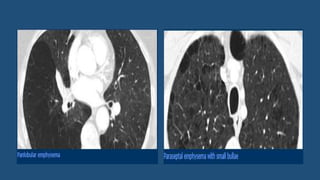

Emphysema

• Emphysema typically presents as areas of low attenuation without

visible walls.

• Centrilobular emphysema

• Most common type

• Irreversible destruction of alveolar walls in the centrilobular portion of the

lobule

• Upper lobe predominance

• Strongly associated with smoking.

• Panlobular emphysema

• Affects the whole secondary lobule

• Lower lobe predominance

• In alpha-1-antitrypsin deficiency + smokers with advanced emphysema

• Paraseptal emphysema

• Adjacent to the pleura and interlobar fissures

• In older patients  a/w centrilobular emphysema

• In young adults  spontaneous pneumothorax